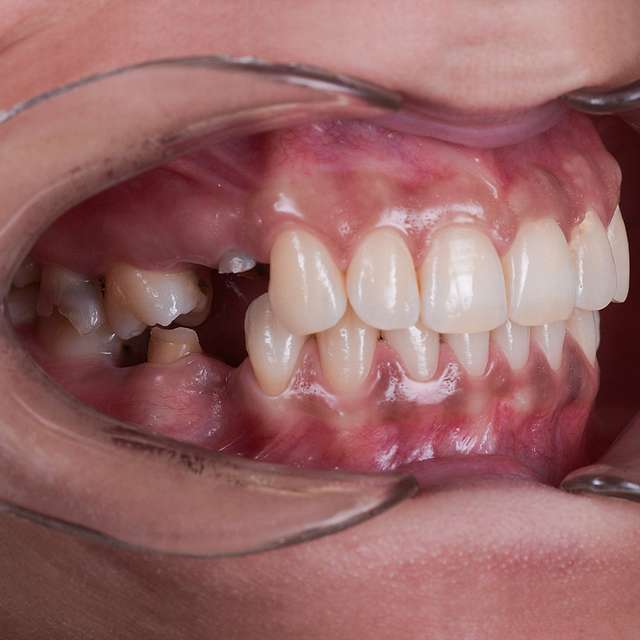

Pentru un rezultat estetic ideal, design-ul final trebuie sa fie intotdeauna referinta pentru chirurgie. Design-ul si computerul tomograf al pacientului sunt compilate pentru a primi pozitia ideala a implanturilor dentare